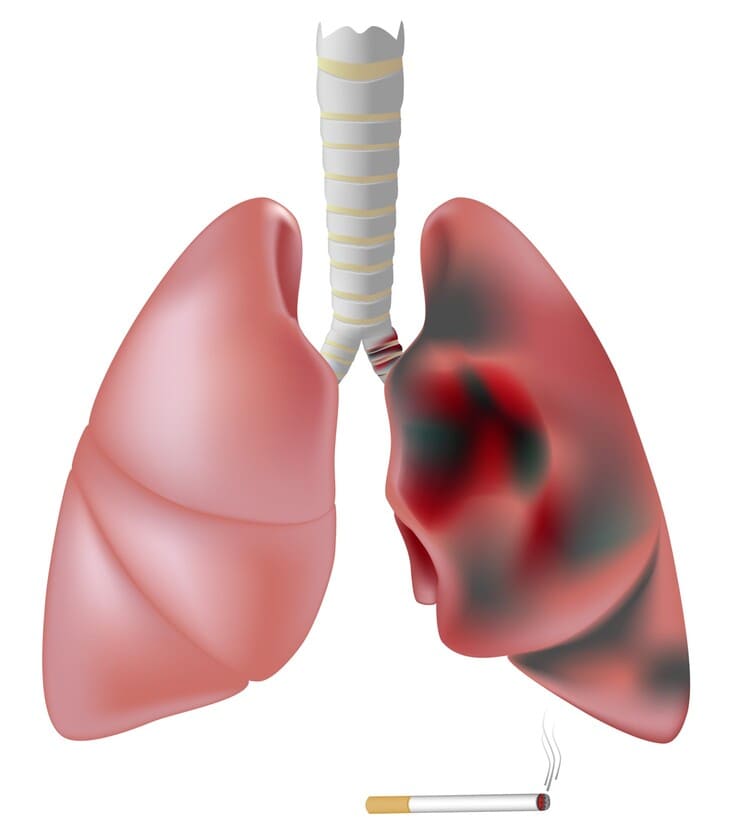

COPD is een chronische longziekte waarbij de longen altijd ontstoken zijn, wat leidt tot blijvende schade aan de longblaasjes. Deze schade is niet meer te genezen. De oorzaken van COPD kunnen onder andere een erfelijke ziekte zijn, maar vooral ontstaan door roken.

3.Teer: blijft achter in je longen als een stroperige laag en kan niet meer uitgehoest worden.

Roken is de belangrijkste oorzaak van COPD, longkanker en hart- en vaatziekten. Elk jaar overlijden ruim 5000 mensen aan COPD en ruim 8000 mensen aan longkanker. Roken is dus zeer schadelijk voor de gezondheid.